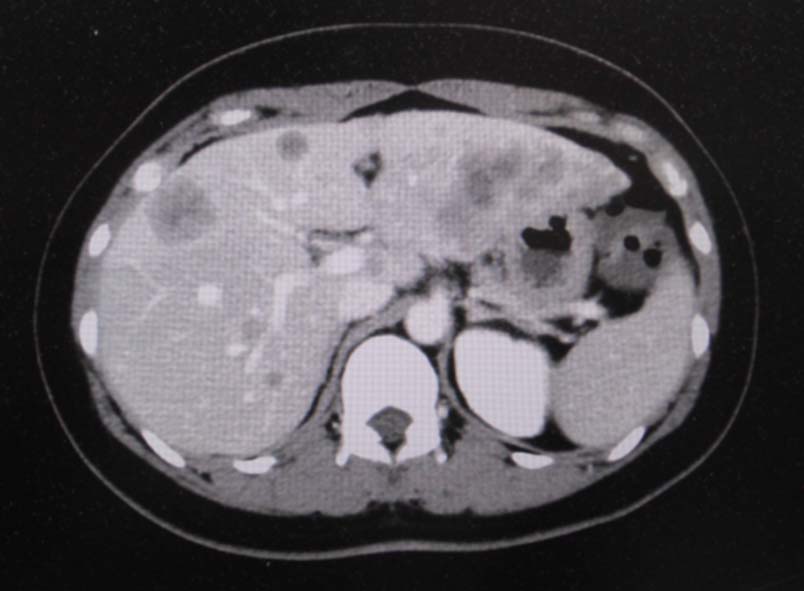

CT画像:左肺から縦隔に及ぶ腫瘍(肺は単独病変. 肺内転移なし.),乳腺腫瘤,子宮腫瘤, 多発肝腫瘤あり.

CT画像および肺腫瘤生検組織